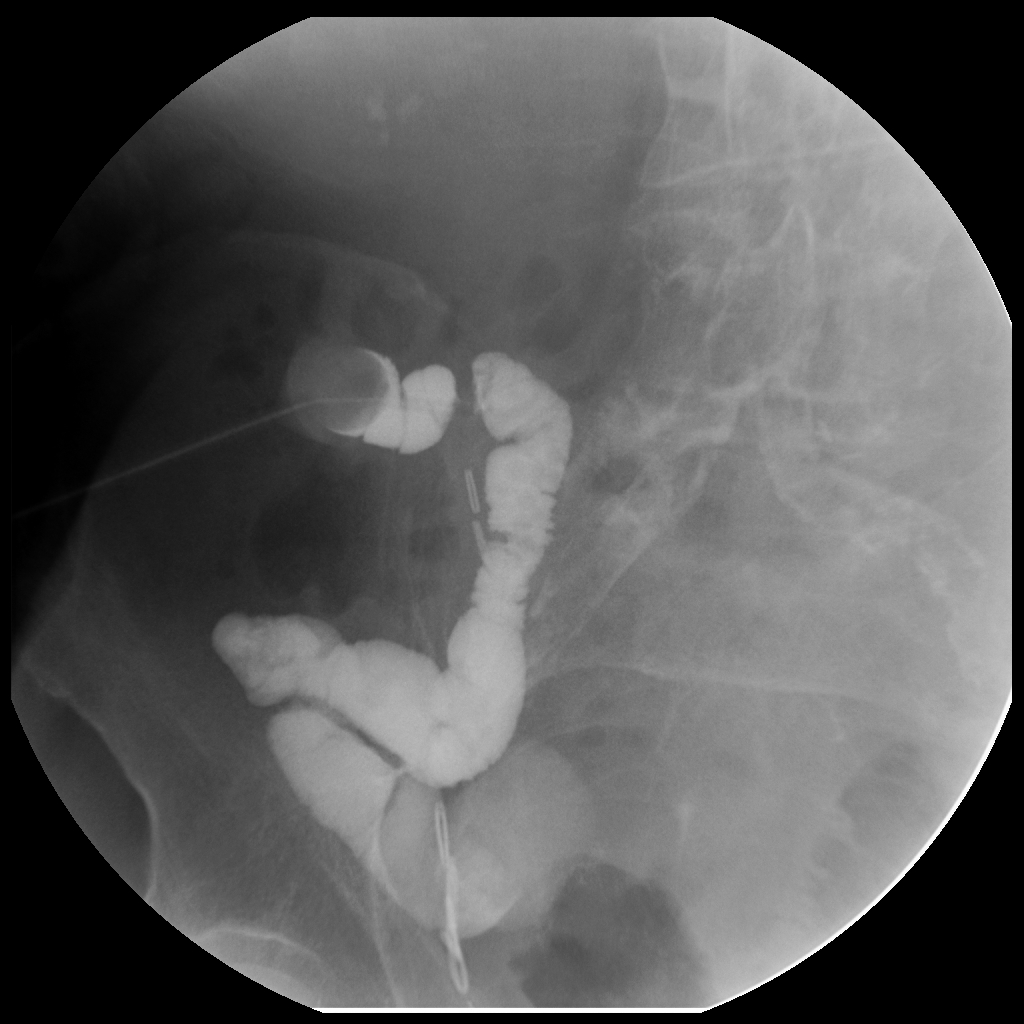

About 15mL - beginning to see retrograde filling of ureters to renal pelvis on patient's right side.

Contrast seen in patient's left renal pelvis after 20mL injected.

Post-drainage KUB with drainage bag reconnected - showing retention of contrast.